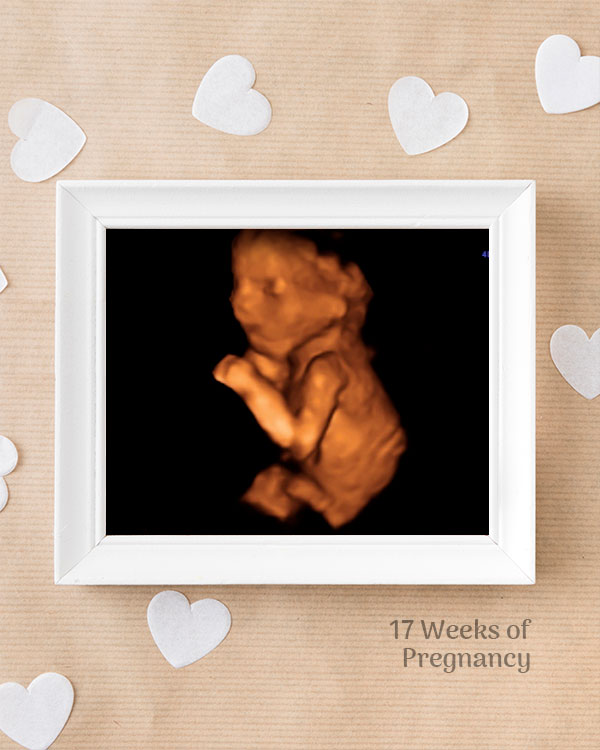

3D / 4D Baby Scan

Mediserv Diagnostics pioneered 4D scanning in the Malabar region. These advanced scans provide realistic images of the baby, allowing detailed evaluation of fetal structures and movements while creating a meaningful bonding experience for parents.